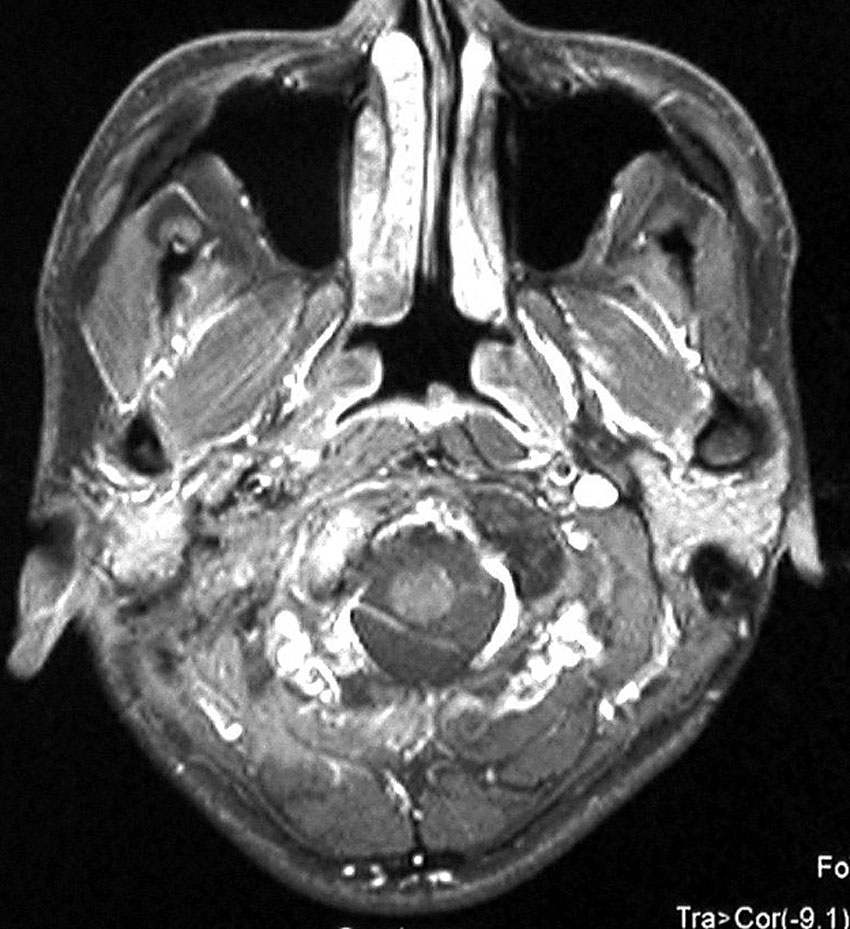

遺伝歴があり30代くらいです。黄色の矢印で示す右側はglomus vagale,左側は上がglomus jugulare、左下がglomus caroticumです。教科書に載せたいくらい典型的な部位に発生しています。無症状ですからもちろん治療はしません。6年くらい経過観察していますがほとんど増大もしません。